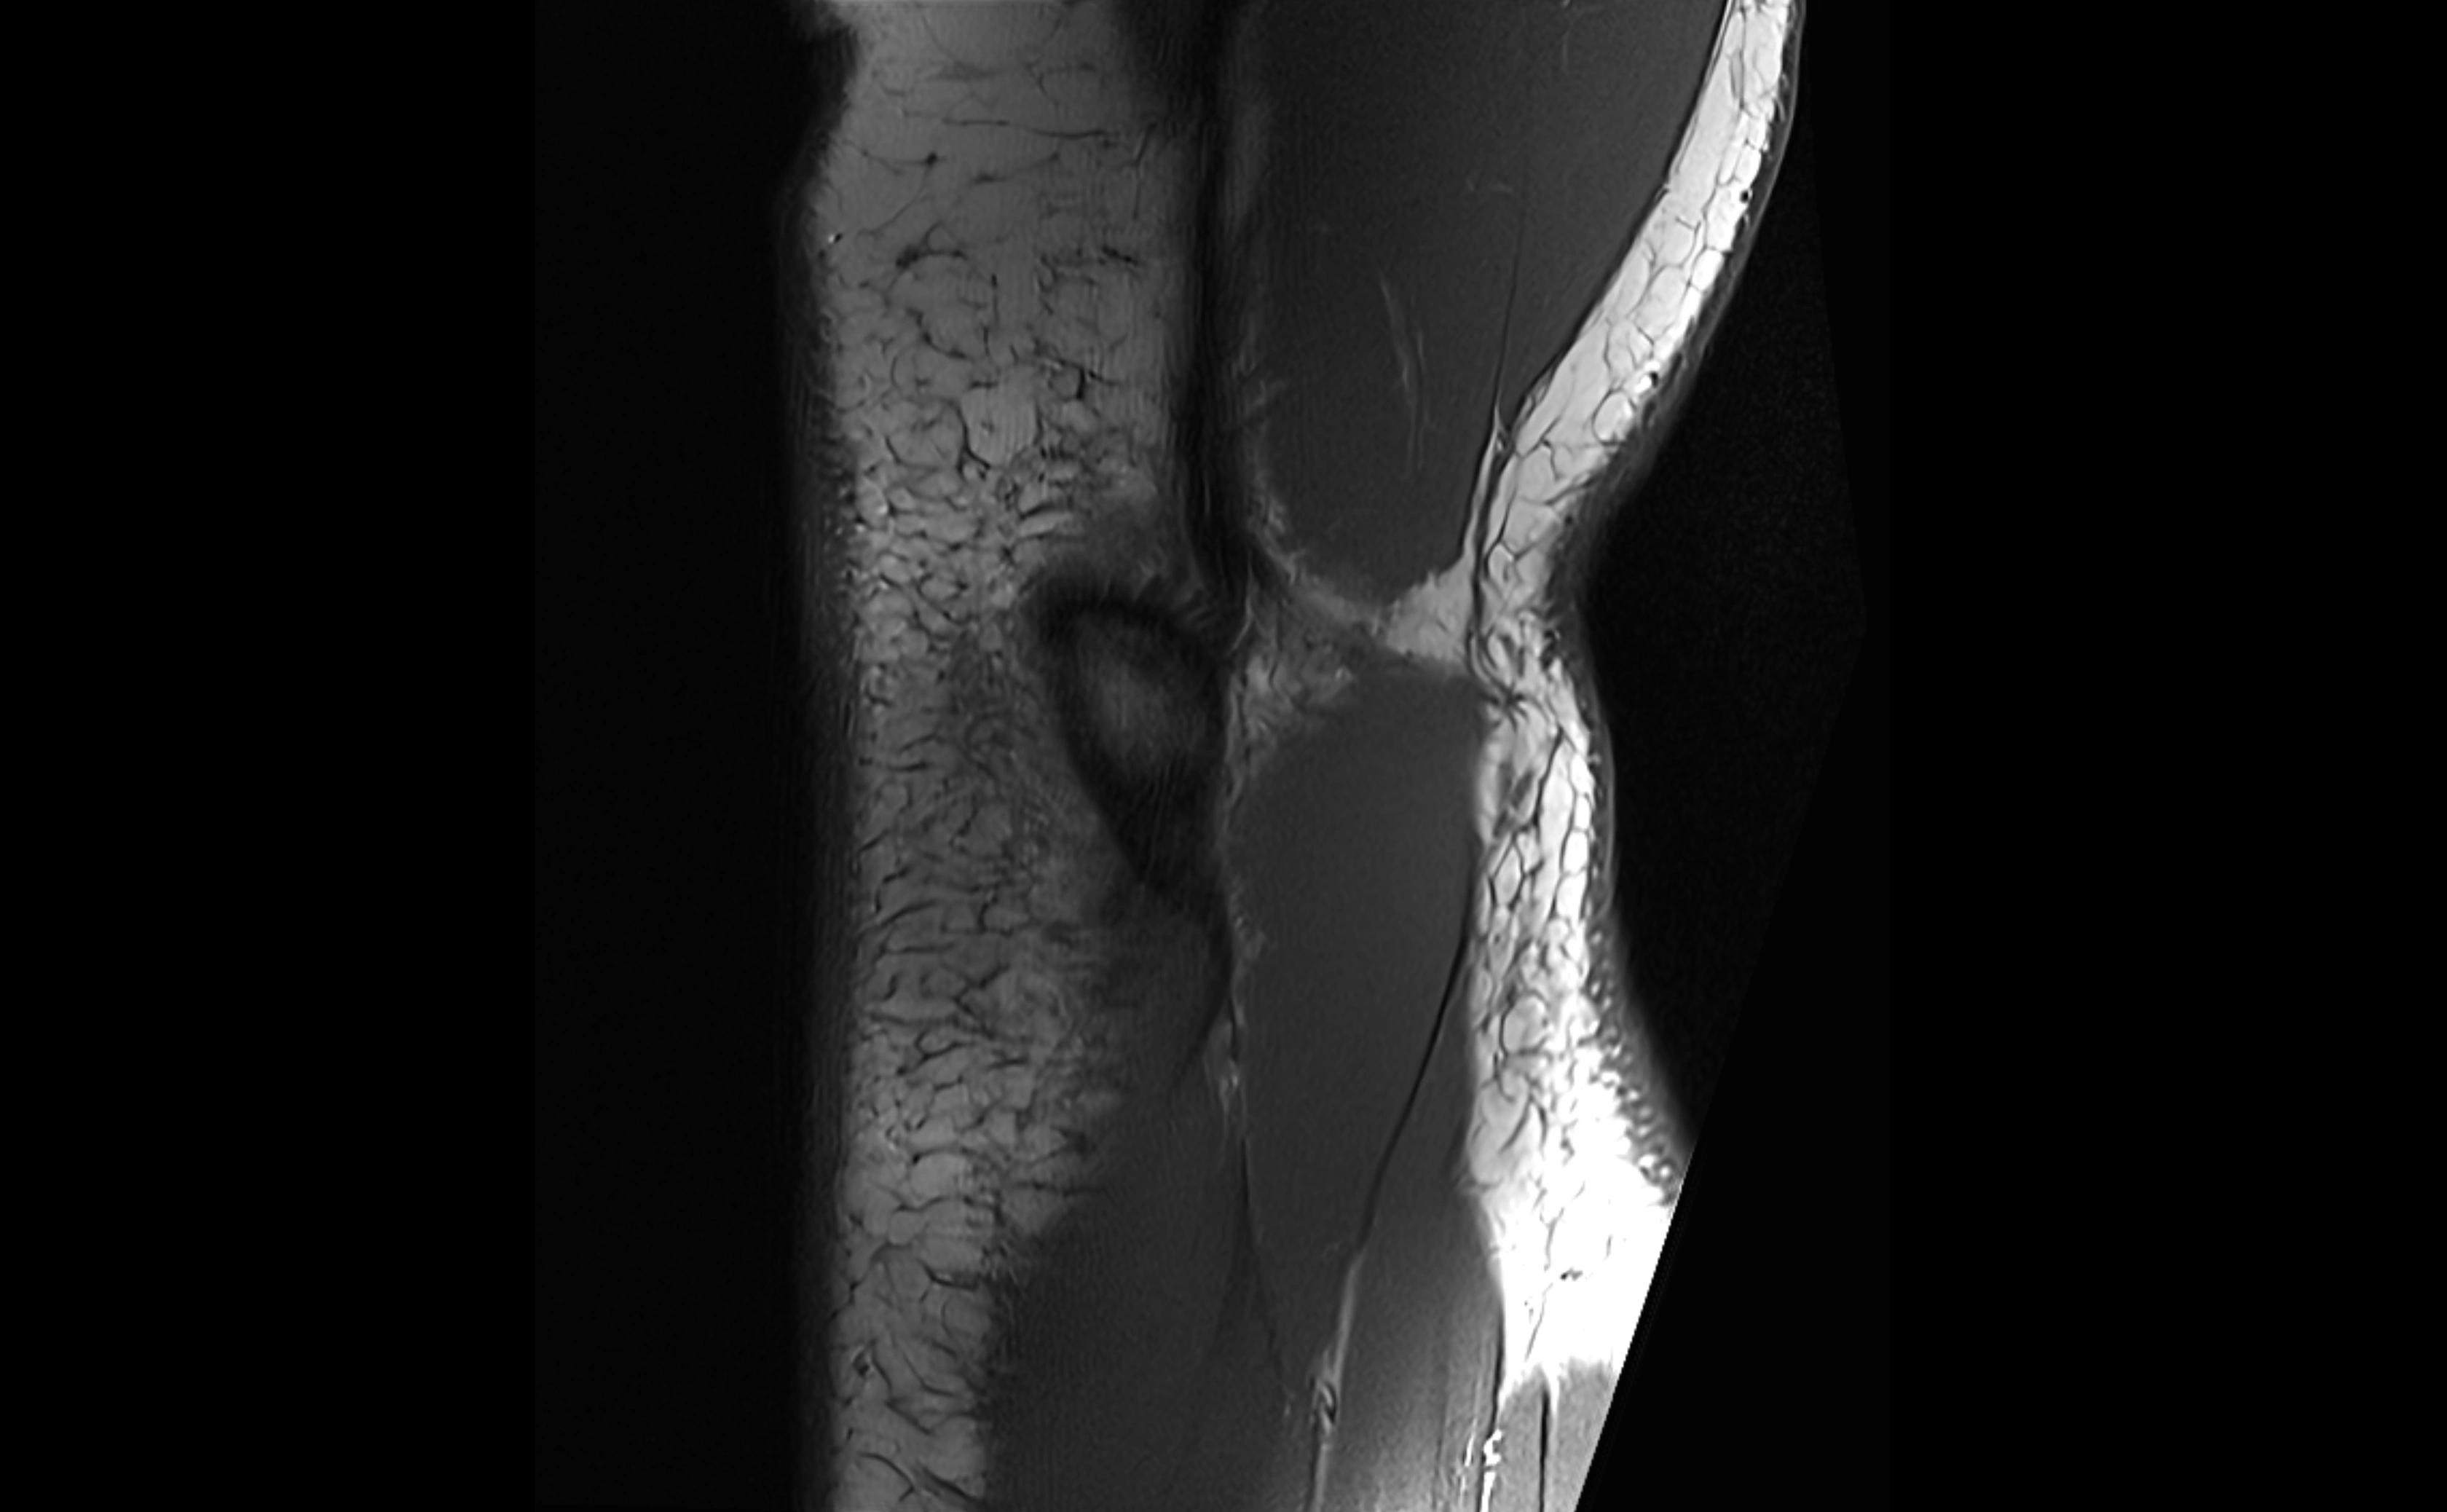

MRI images

image